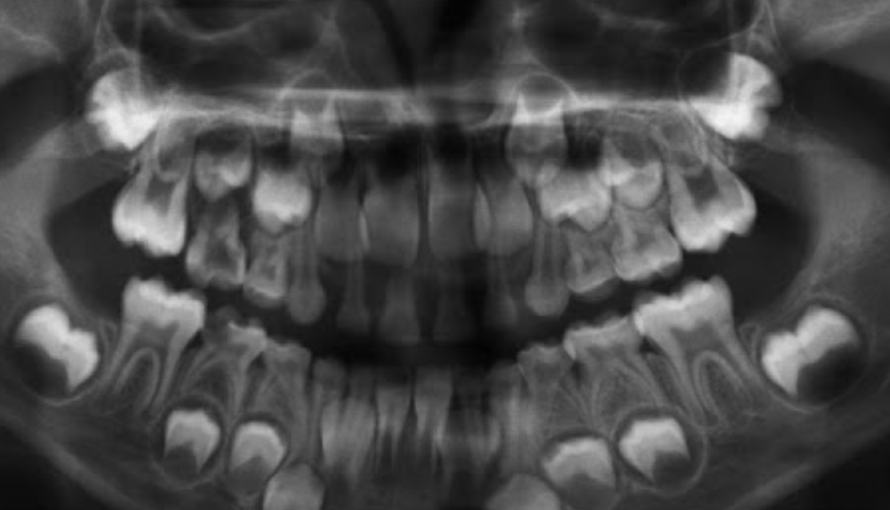

Permanent lower incisors present? Yes, so definitely 6-7

Permanent upper Incisors not erupted yet. Therefore not 7-8 y.o.

Conclusion = 6 y.o